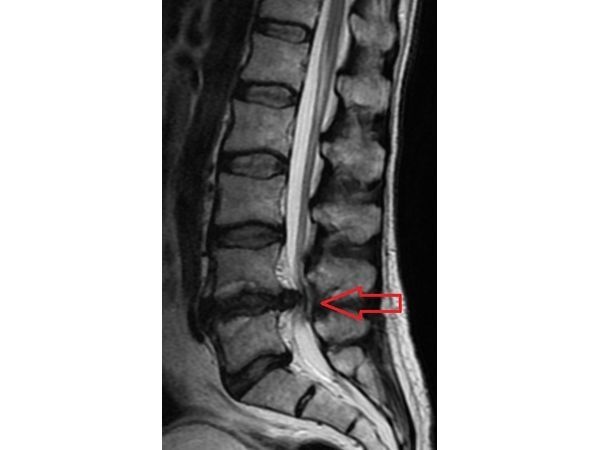

По результатам МРТ поясничного отдела позвоночника:

- дегенеративно дистрофические изменения;

- задняя грыжа диска на уровне позвонков L4–L5;

- задняя протрузия (выпячивание) дисков L3–L4, L5–S1;

- просвет спинномозгового канала полностью закрыт на уровне позвонков L4–L5.

Обострение хронического диффузного остеохондроза позвоночника. Задняя грыжа диска на уровне L4–L5. Задняя протрузия дисков L3–L4, L5–S1. Абсолютный стеноз спинномозгового канала на уровне L4–L5. Люмбоишиалгия (боль в пояснице из-за поражения седалищного нерва) слева. Радикулопатия L5 слева. Парез левой стопы.